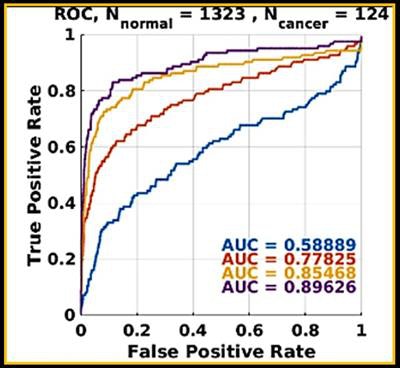

Before and after training the software with deep learning on 187 biopsy-proven cases, the researchers tested the CAD algorithm on 7,232 digital 2D screening mammograms and generated receiver operating characteristic (ROC) curves to assess its performance.

Early breast cancer was flagged by the CAD software three years prior to biopsy and showed a progressive increase in quantitative score over the three years. All images courtesy of Dr. Alyssa Watanabe.In other results, the researchers found that progressive deep-learning training continued to improve the performance of the CAD software over time for breast masses.

Progressive machine learning also improved the software's accuracy for breast masses, as demonstrated by increasingly higher areas under the ROC curve after training.

Progressive machine learning also improved the software's accuracy for breast masses, as demonstrated by increasingly higher areas under the ROC curve after training."As more and more cases of biopsy-proven breast cancers and benign lesions are entered into the data bank, the CAD 'learned' to distinguish between these lesions with greater and greater accuracy," the authors wrote in their poster at ECR 2017. "The potential to enter massive amounts of ground truth cases could lead to greater and greater accuracy in flagging cancers and not flagging benign lesions such as fat necrosis."